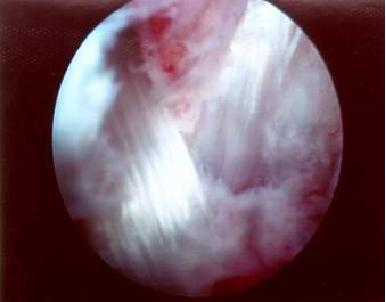

4、软骨剥脱:

软骨剥脱

上图是软骨剥脱,是膝关节炎的典型症状,我们可以通过关节镜检查来诊断。

并可以通过关节镜下的清理及精准药物注射来实现对膝关节的治疗。

单纯的膝关节炎症,我们可以大量生理盐水进行冲洗,以冲走关节内大量的带有炎性的组织。并对退变的半月板及滑膜进行修整。

从而让膝关节炎症得到缓解并延缓膝关节炎的进程。